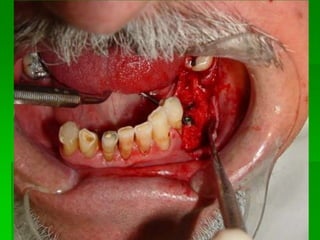

On Lay

Sinus Liftimg

Avaliação da Altura e Largura óssea